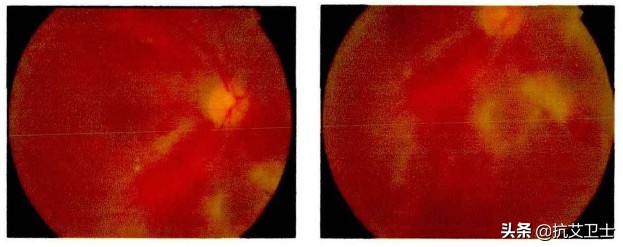

巨细胞病毒感染

其中最为多见的为巨细胞病毒感染,中国东部地区,HIV 患者巨细胞病毒视网膜炎患病率占 HIV相关眼部并发症的 10. 5%[9]。巨细胞病毒视网膜炎是全层视网膜感染,病变最先累及周边视网膜[10],是AIDS晚期最严重、最常见的眼部并发症[4]。

巨细胞病毒性视网膜炎

最常见的表现为视力明显下降,眼前黑影飘动或视野缺损[11]。进行抗病毒治疗能减缓巨细胞病毒视网膜炎的发展速度,多数患者可达到临床治愈[12],大部分视力水平可以得到恢复,但是很难恢复到未感染时期。